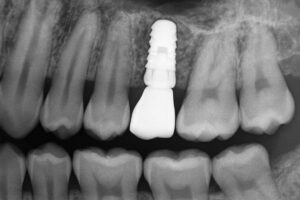

Many patients ask about “popular dental implants” when they need tooth replacement. Popular dental implants are titanium or ceramic posts placed into the jaw to